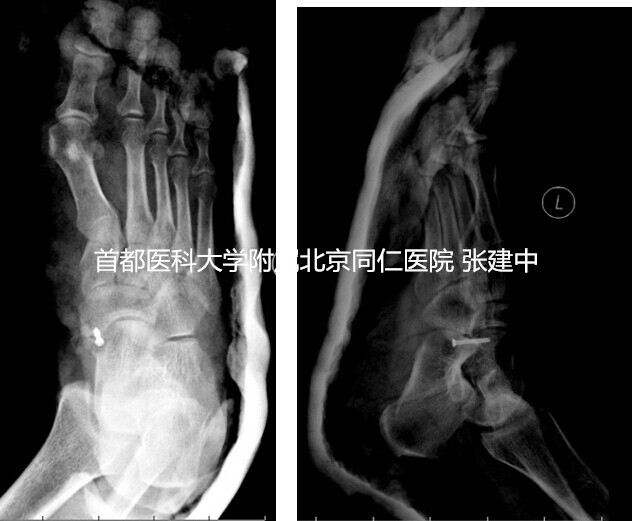

图3. 示副舟骨与舟骨融合,患足石膏外固定

据此,手术方案制定为副舟骨与舟骨融合术。术中在足内侧以舟骨结节为中心做一纵行切口,长约4-5cm,显露舟骨结节及副舟骨,探查见副舟骨上的胫后肌腱止点完整,未见明显炎性改变,予以仔细保护。探查见副舟骨与舟骨之间存在明显的纤维连接,牵拉胫后肌腱时二者之间存在微动。以摆锯与咬骨钳仔细去除副舟骨与舟骨之间的纤维连接直至暴露出新鲜出血的骨面,将带有胫后肌腱的副舟骨部分骨块向远端及跖侧轻度移位,确保两端骨面对合良好后以空心螺钉固定,达到骨性融合。C臂透视再次确认内固定可靠,且螺钉位于舟骨内未突入临近关节面后,逐层修复周围软组织。术后患足石膏外固定4周(图3),去除外固定后开始免负重下活动。术后6周X线检查示内固定位置可靠后开始部分负重,术后3个月开始完全负重。